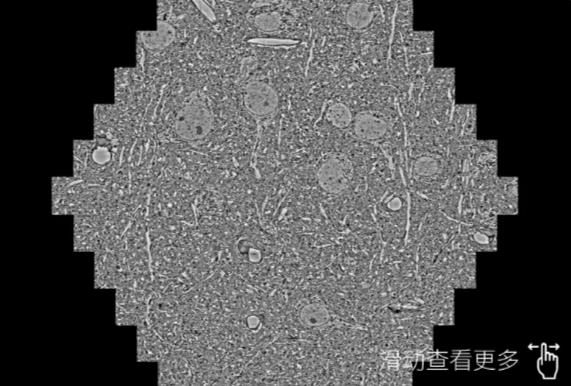

鼠脑切片。左图使用安徽蔡司安徽扫描电镜MultiSEM706对165μmx143pm面积区域成像,耗时仅需1.5秒。右图为鼠脑切片中30μm区域放大效果。样品由芝加哥大学B.Kasthuri提供。

使用蔡司高速安徽扫描电镜MultiSEM对1mm²人脑皮层组织进行高分辨成像,并对其中的各种细胞结构进行三维重构分析。左图展示了2x3mm²组织平面中锥体神经元的三维重构效果。右图显示了局部体积神经元三维重构。图像由哈佛大学chtman实验室提供,渲染图由D. Berger 制作。